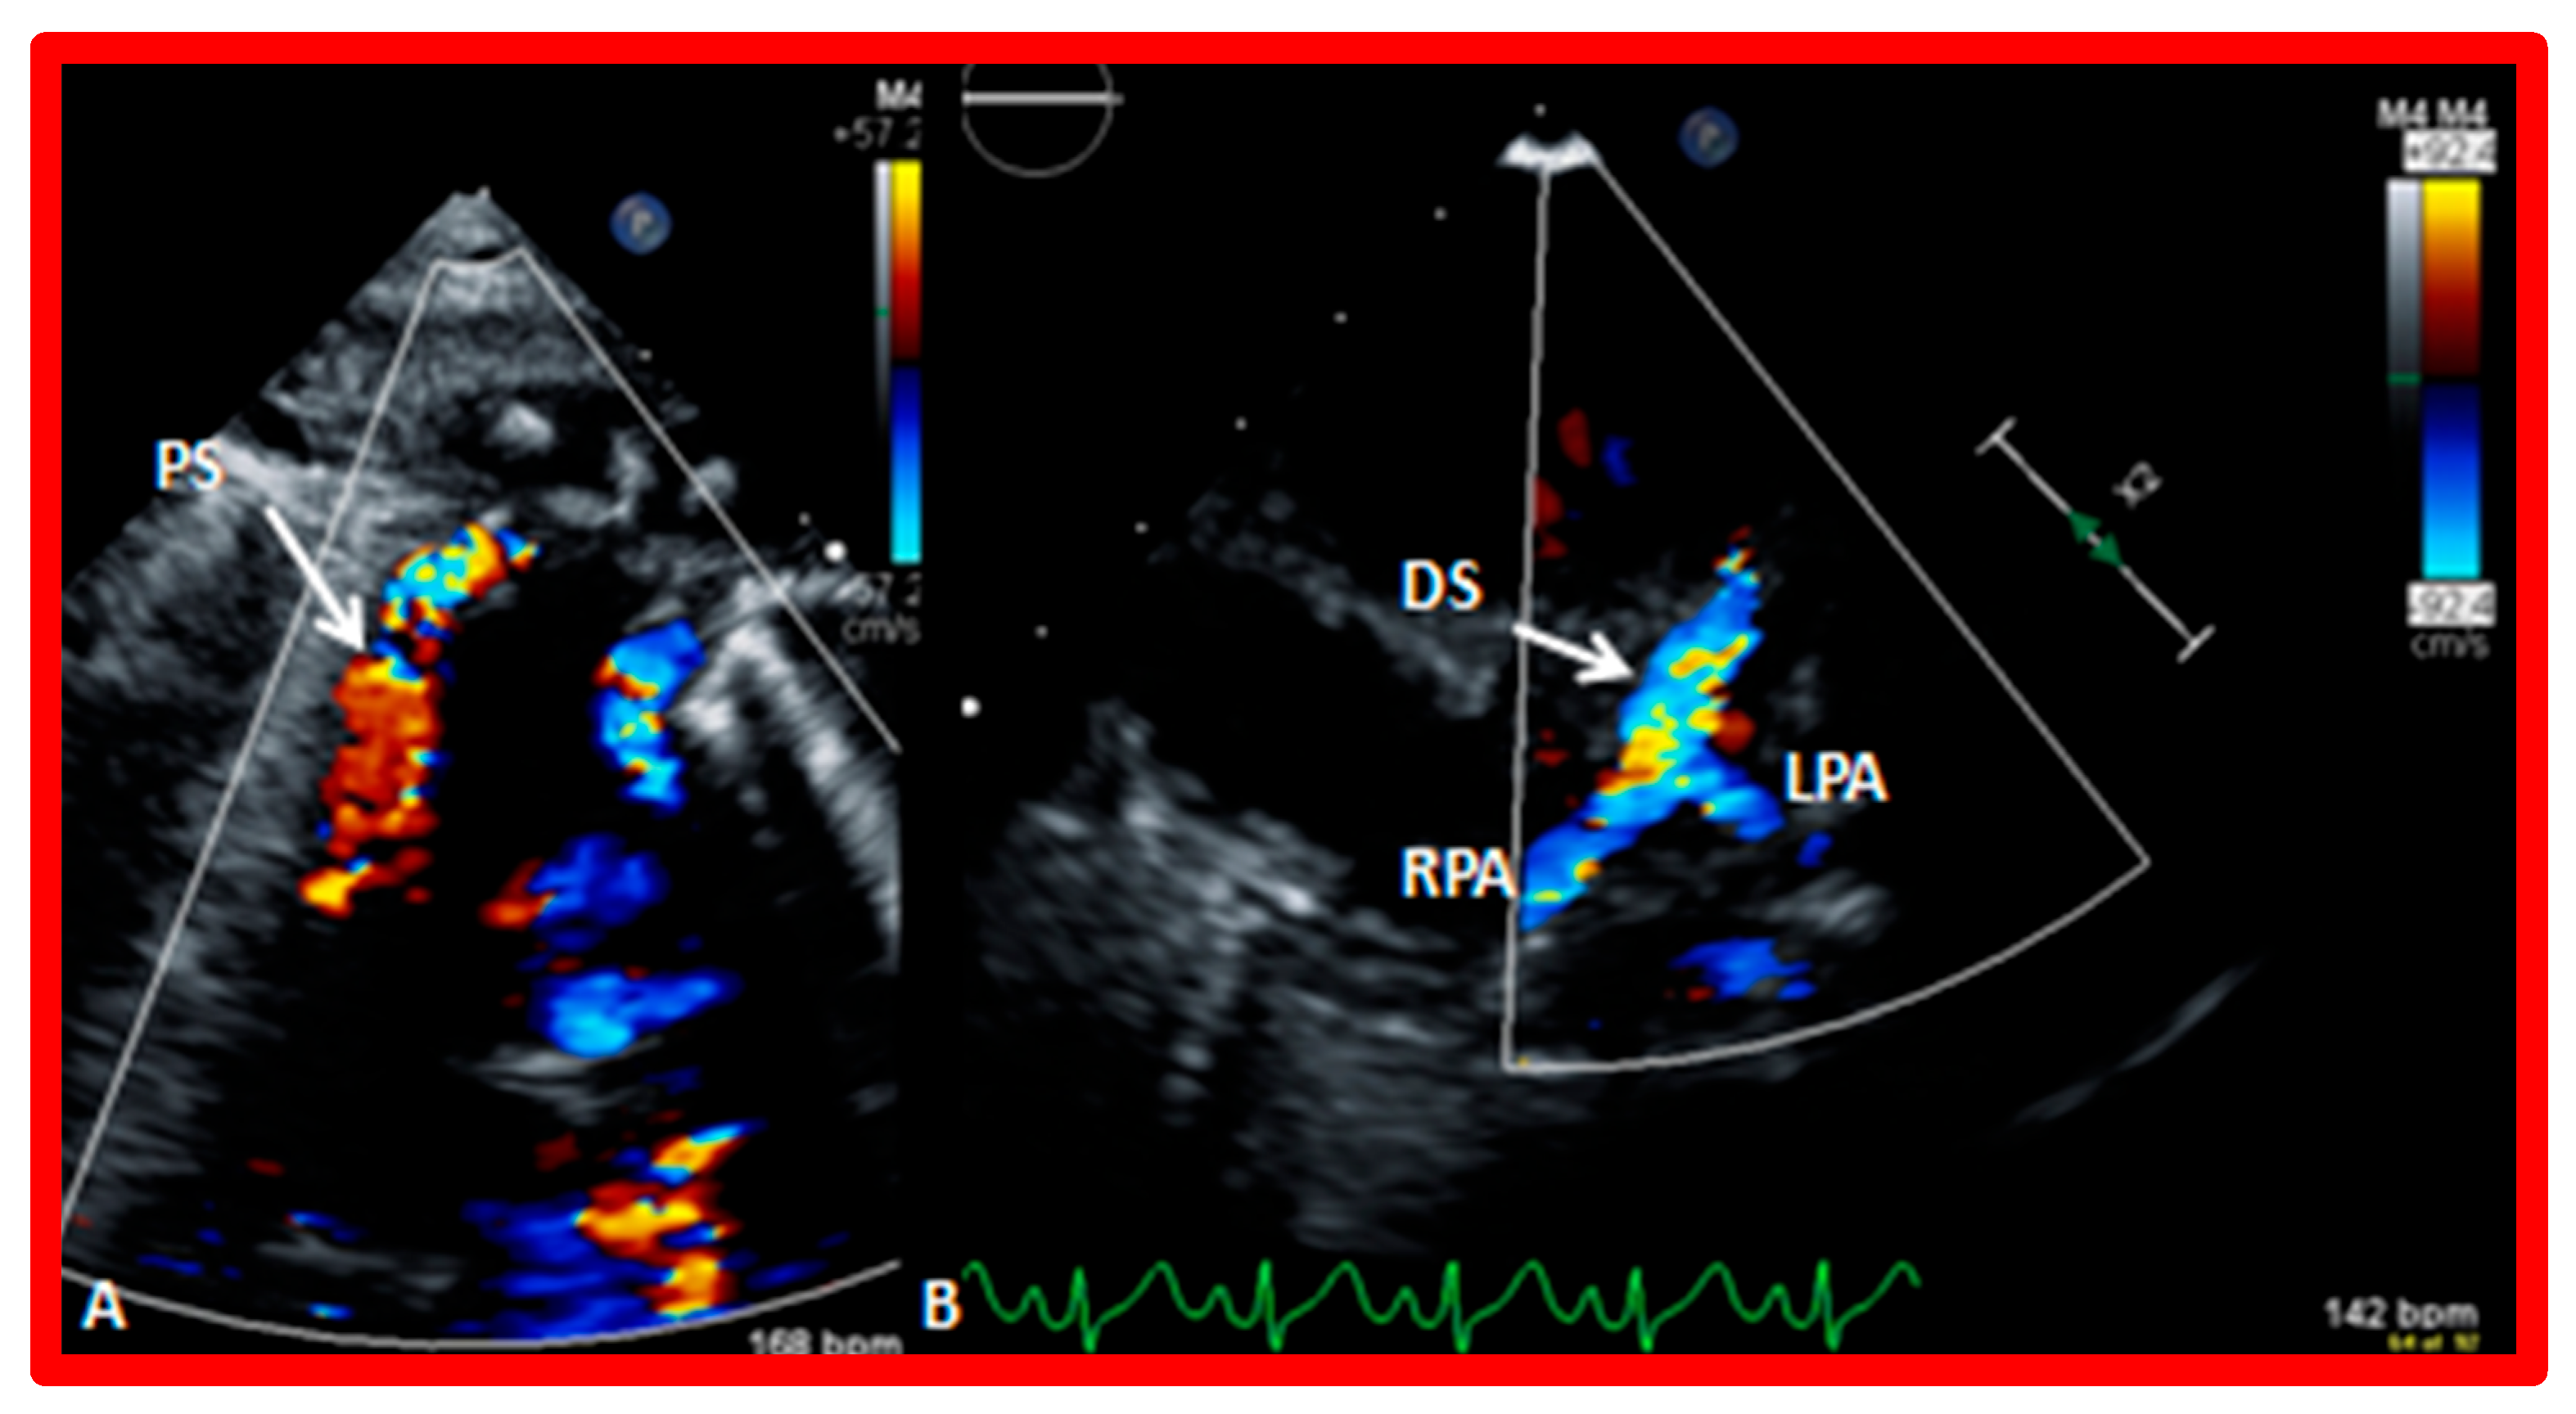

- Mazur, L.; deYbarrondo, L.; Pickard, L.; Rao, P.S. Development of supravalvular pulmonary artery stenosis following a Nuss procedure. J. Pediatr. Surg. 2012, 47, e61–e64. [Google Scholar] [CrossRef] [PubMed]

- Muller, W.H., Jr.; Danimann, J.F., Jr. The treatment of certain congenital malformations of the heart by the creation of pulmonic stenosis to reduce pulmonary hypertension and excessive pulmonary blood flow, a preliminary report. Surg. Gynecol. Obstet. 1952, 95, 213–219. [Google Scholar]

- Afifi, A.R.S.A.; Seale, A.N.; Chaudhari, M.; Khan, N.E.; Jones, T.J.; Stumper, O.; Botha, P. Pulmonary artery banding: Still a role for staged bi-ventricular repair of intracardiac shunts? Cardiol. Young 2022, 14, 1–7. [Google Scholar] [CrossRef]

- Agasthi, P.; Graziano, J.N. Pulmonary Artery Banding. 1 October 2022. In StatPearls; StatPearls Publishing: Treasure Island, FL, USA, 2023. [Google Scholar]